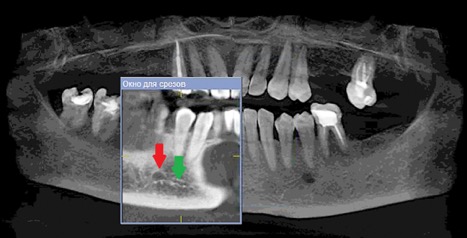

Данные осложнения происходят из-за повреждения резцовой петли – внутрикостного продолжения нижнелуночкого нерва (Рис. 1a и 1b), которая начинается от ментального отверстия и заканчивается индивидуально, как правило, на уровне латерального или центрального резца [1].

Рисунок 1а: КЛКТ. Панорамный реформат.

(Зеленая стрелка – резцовая петля, красная стрелка – подбородочное отверстие.)